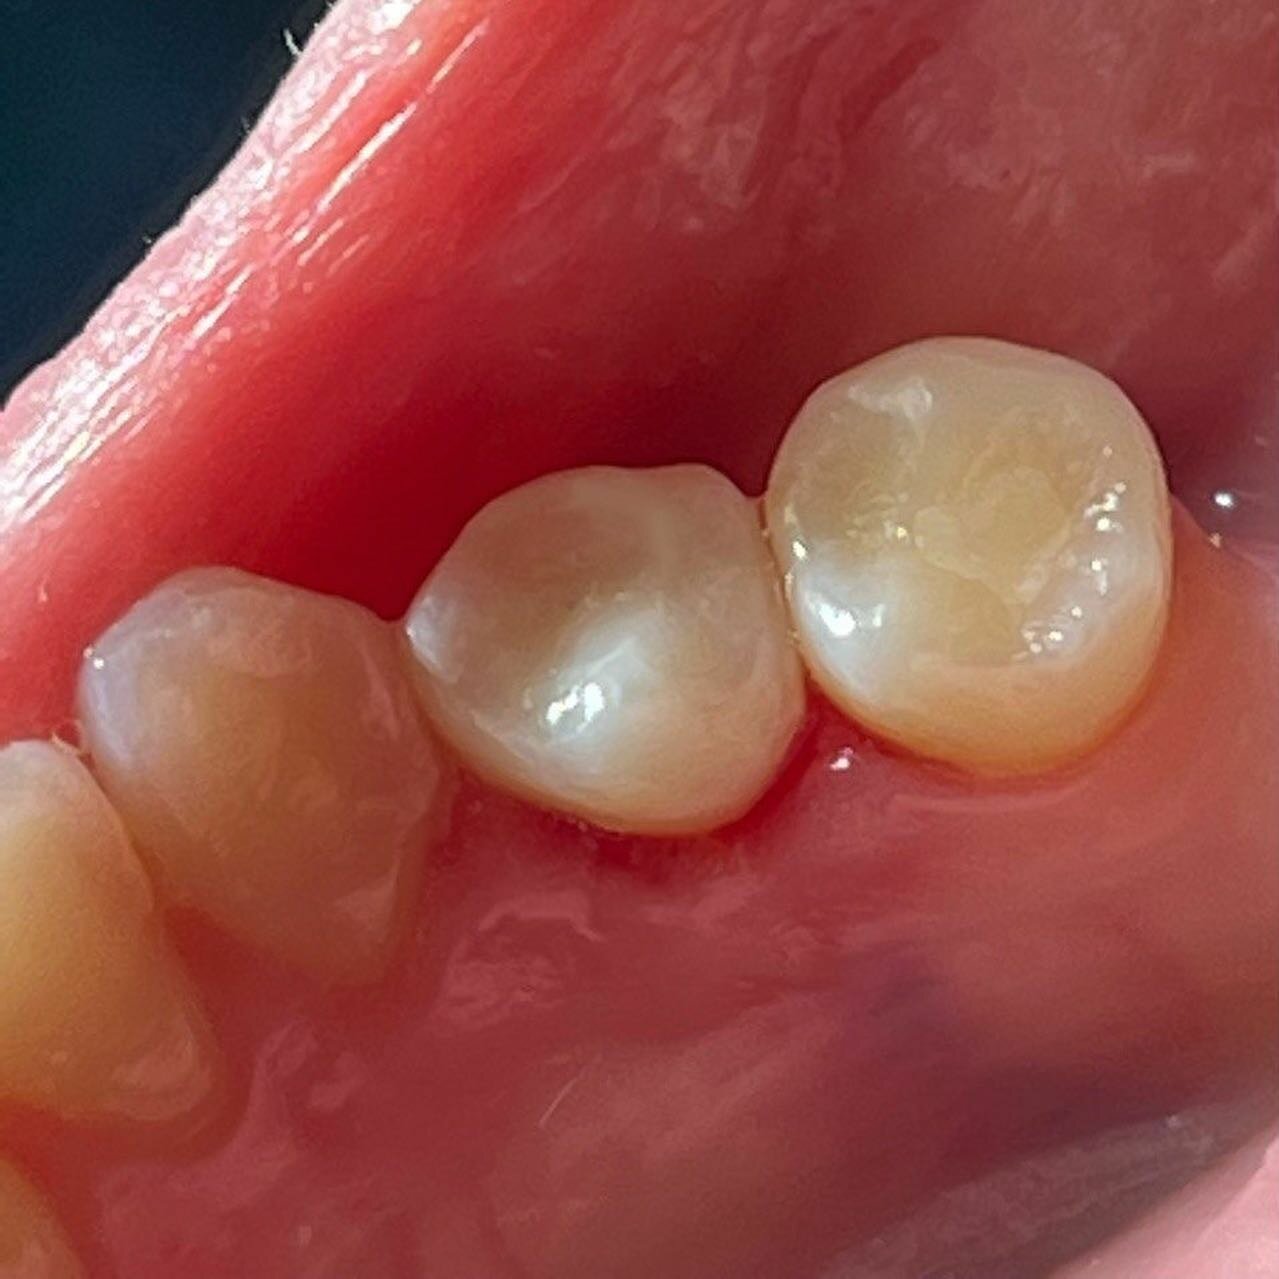

Вылечили кариес двух зубов быстро и профессионально. Врачи грамотные, оборудование новейшее. Ситуация была достаточно запущенная, но за несколько посещений все сделали. Обошлось без удаления, чему я очень рад. Теперь только сюда буду обращаться.